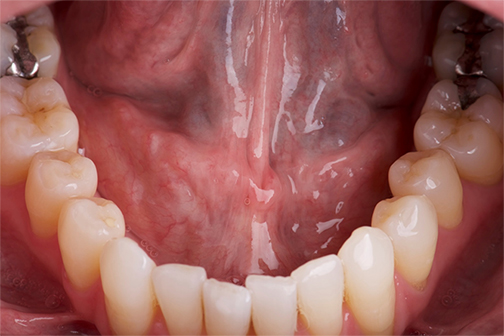

LSU Health New Orleans Welcomes New Dental School Dean

After a national search, Interim Chancellor Steve Nelson, MD, CM, appointed Angelo J. Mariotti, DDS, PhD, Dean of the LSU Health New Orleans School of Dentistry. Dr. Mariotti began his new role on January 3, 2023. More

UCP & LSU Health Dental School Partner to Care for Children and Adults with Special Needs

United Cerebral Palsy of Greater New Orleans has donated $100,000 to support education, patient care and community outreach at LSU Health New Orleans School of Dentistry, benefiting children and adults with special needs. More